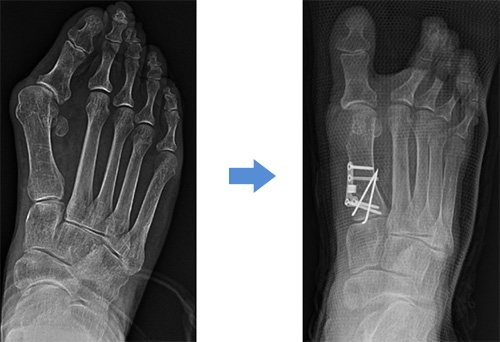

1. 엄지발가락이 바깥쪽으로 휘고, 염증으로 통증 발생

2. 발바닥에 굳은살이 생기고, 발바닥에 통증 발생

3. 엄지발가락과 두번째 발가락이 겹쳐지거나 탈구

4. 새끼발가락 관절이 돌출되는 변형

1. 엄지발가락을 바깥쪽으로 당기는 힘줄과 인대를 절단하여 변형을 막고

2. 돌출된 뼈는 제거하고

3. 각도 교정을 위해 절골술 시행